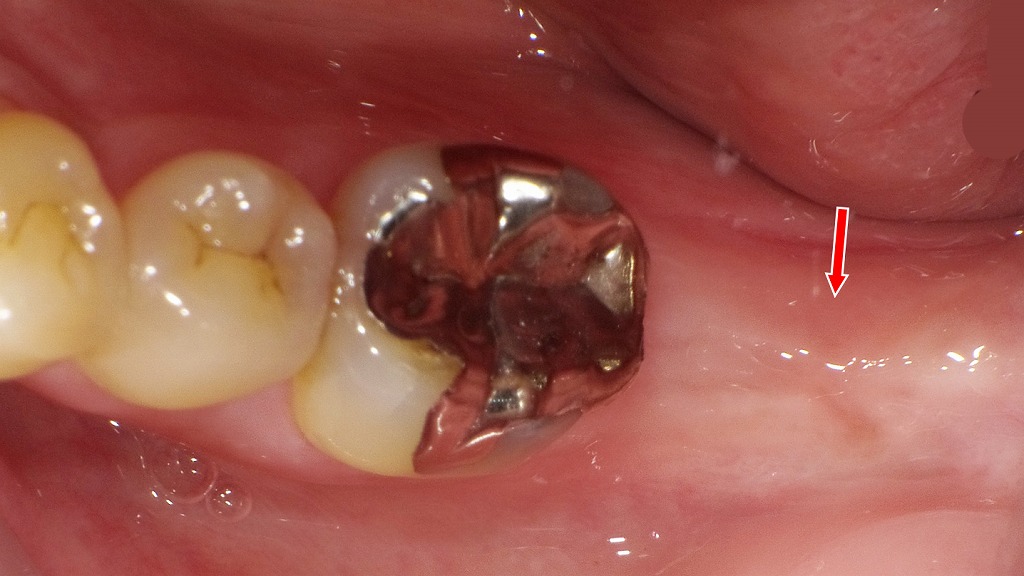

下顎7番抜歯後に起こる変化と対策― 上顎7番の挺出を防ぐための治療経過 ―

下顎7番を抜歯すると、欠損部の歯肉は治癒していきますが、噛み合う相手を失った上顎7番は徐々に挺出しやすくなります。挺出が進行すると、咬合の乱れや将来的な補綴治療の妨げとなる可能性があります。本症例では、抜歯後にインプラントを埋入し、咬合支持を早期に回復することで、上顎7番の挺出を抑制しています。下顎臼歯部の欠損は、周囲や対合歯への影響が大きいため、抜歯後は経過観察だけでなく、将来を見据えた適切な治療選択が重要です。